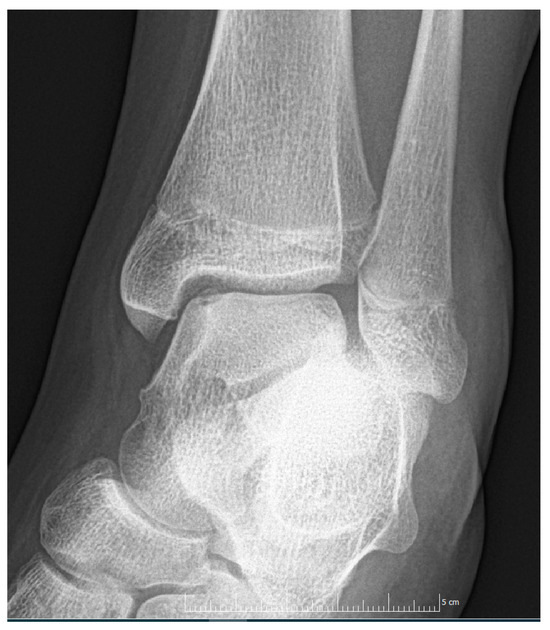

Juvenile Osteochondritis Dissecans: A Case Report